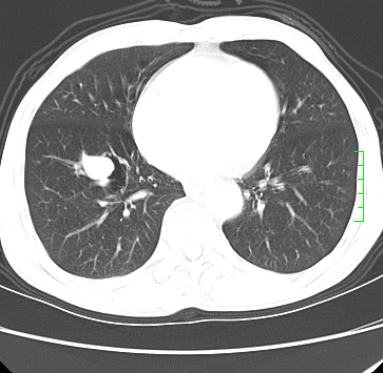

m,73y。膝关节疼痛伴双下肢水肿。入院常规胸片发现结节灶。增强为静脉期。

浅分叶、棘突,考虑右下肺周围型肺癌

考虑周围型肺癌  ,双上肺结核。

肿块周围可见局限性气肿,考虑肺癌可能性大。双肺上叶继发型肺结核。

指套征,强化明显,近侧肺组织局限性肺气肿,考虑支气管类癌,慢支、肺气肿、双上陈旧性tb、冠脉钙化。

鉴别:先天性支气管闭锁,变态反应性支气管肺曲霉菌病,肺癌,支气管囊肿,支扩黏液嵌塞。

1)考虑右肺下叶周围型肺癌。2)右肺上叶及左肺感染性病变(结核可能)。3)肺气肿。4)冠状动脉钙化。